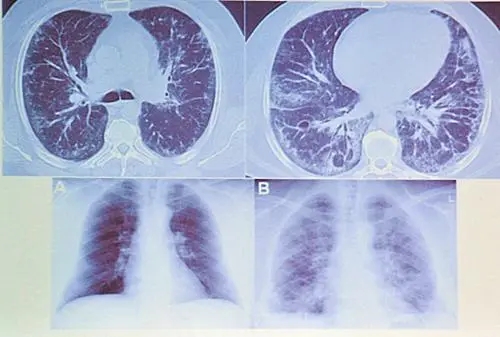

胸部X線檢查可見肺內特征性的肺炎陰影。然而,與細菌性或病毒性肺炎不同。在系列X線檢查時,嗜酸性肺炎的特點為肺內病灶的形成和消散均較迅速。痰液顯微鏡檢查可見大量成團的嗜酸性細胞,而不是細菌性肺炎時的中性粒細胞。其他的嗜酸性肺炎的檢查亦有助于尋找病因,特別是對真菌或寄生蟲感染;這類檢查包括糞便顯微鏡檢查。亦應考慮有無致病的藥物因素。